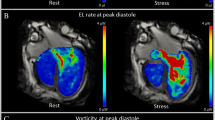

Kinetic energy and energy loss were calculated in a custom-developed software, as previously described [23]. Both parameters were calculated at node level in the 3D domain and then were integrated in a volume of interest, and then normalized by volume (uW/ml) (Fig. 1). KE represents the amount of energy that the blood flow possesses due to its motion; EL represents the amount of KE within the blood flow lost per second due to viscosity-induced frictional forces [3]. In addition, EL index (EL/KE) was calculated as the ratio of normalized EL/normalized KE. EL index (EL/KE) has been described, which can be used as a marker of flow efficiency [7].

Flow Energetics Parameters

Flow energetics of the Fontan circuit were evaluated in the caval veins confluence area, where a higher proportion of KE is dissipated, caused by the confluence of different flows [7]. We focused on EL/KE index that reflects the energy dissipated in comparison with the energy presented due to motion, instead of evaluating EL, which increases with the increase of the blood flow in Fontan circulation [4]. EL/KE index in the Fontan confluence was higher in patients with pulmonary branches stenosis or hypoplastic diameters in line with previous studies that evaluated Fontan hemodynamics by computational fluid dynamics analysis and highlight that undersized pulmonary arteries or Fontan pathway stenosis did have a detrimental effect on power loss [4].